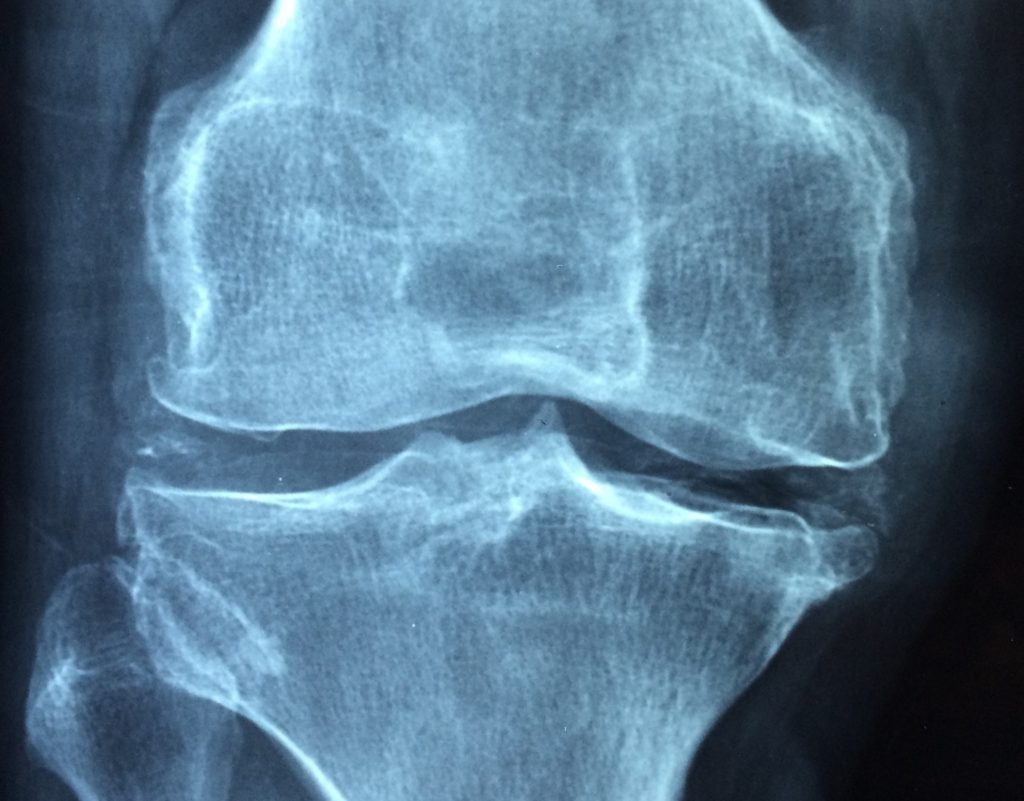

Kenali Jenis-jenis Penyakit Rematik

(Ilustrasi)

Rematik adalah penyakit yang menimbulkan rasa sakit akibat otot atau persendian mengalami peradangan dan pembengkakan. Dikutip dari Medical Xpress, Sabtu (25/9/2021), ada sejumlah jenis rematik yang dialami manusia, dan berikut ini empat penyakit rematik umum di antaranya: Spondilitis ankilosa, asam urat, artritis idiopatik remaja, dan lupus.